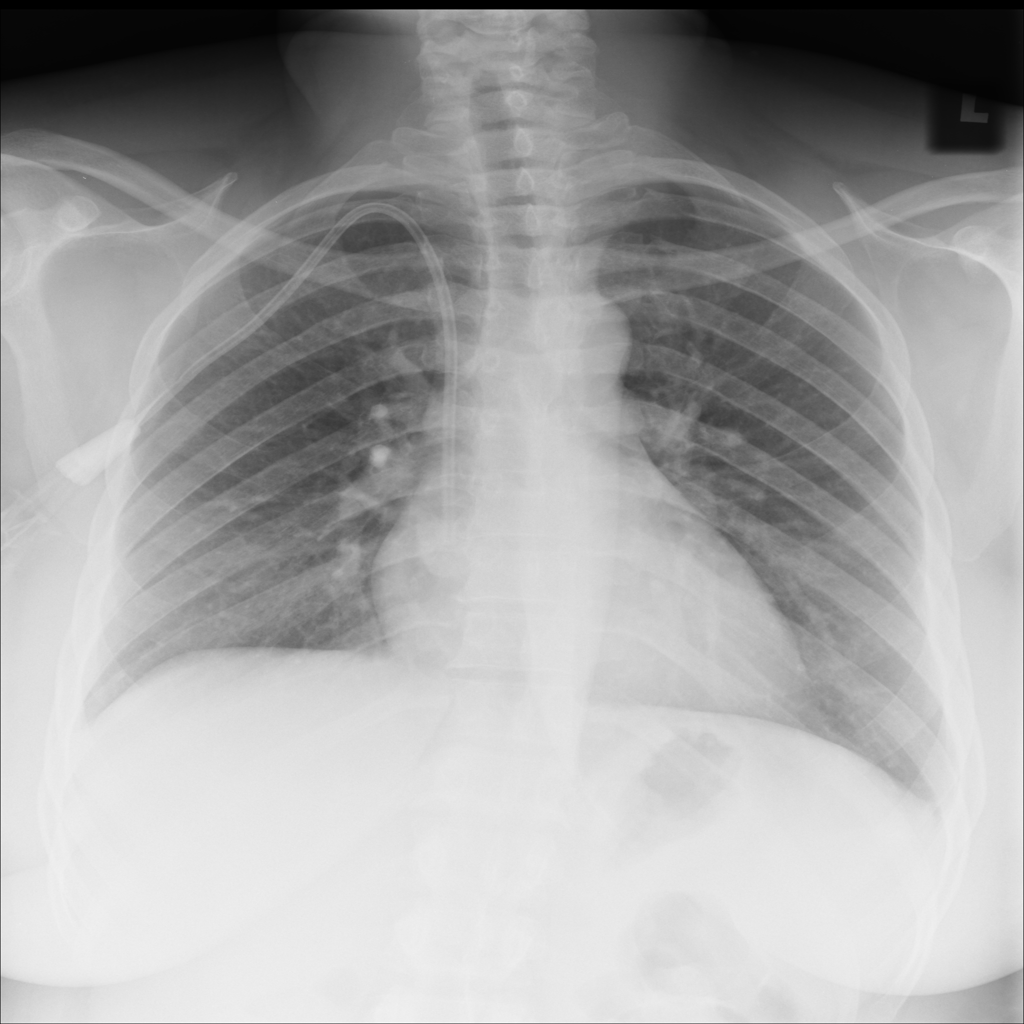

Showing up to 90 reference images for Cardiomegaly.

PAT-AE5C · IMG-000Cardiomegaly

PAT-AE5C · IMG-000

PA